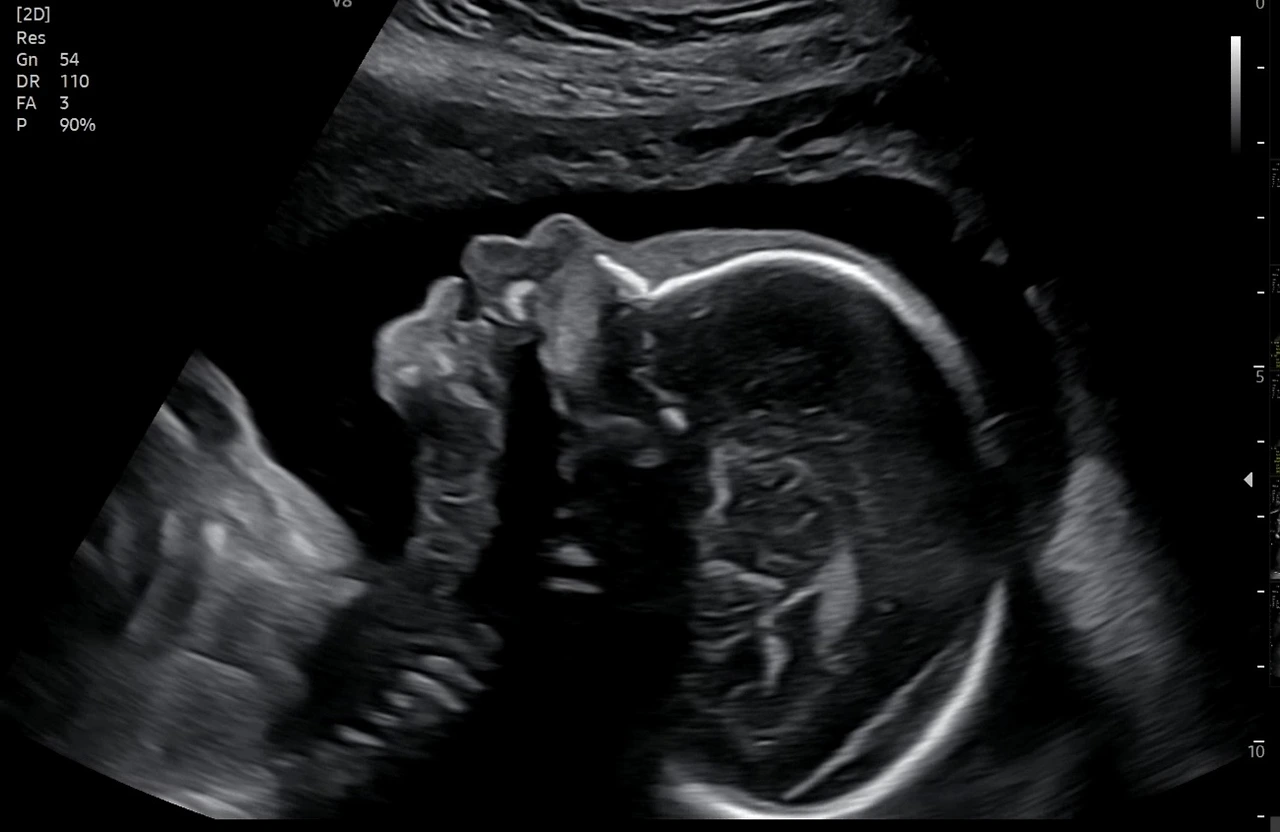

심바 출산까지 100일..

니프티 검사, 정밀 초음파까지 마치고 난 다음에야 온전히 새로운 생명에 대해 기쁜 마음이 들었던 것 같다.

마음 편하게 먹고.. 심바가 건강히 크기만을 오늘도 기다린다.